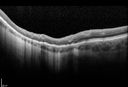

OD Albinism with foveal hypoplasia2202 views28 year old female latina with vision of 20/400Mar 05, 2013